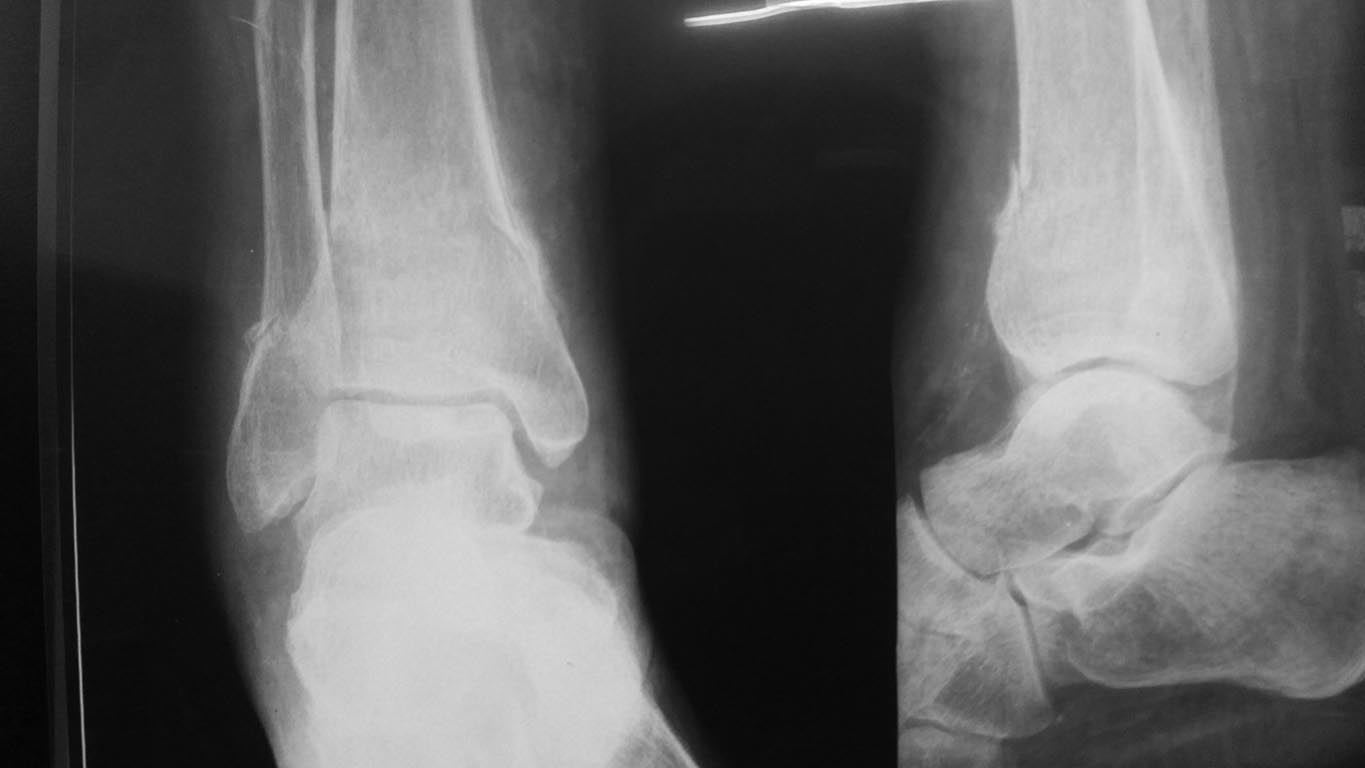

Лечилась амбулаторно с Ds: закрытый перелом костей правой голени в нижней трети без смещения. Повторную травму исключает. На контрольных Rg выявлено смещение отломков, признаки консолидации.

А Вы то какой диагноз ставите? От чего сломалось? Ренальная остеодистрофия на фоне ХПН с гемодиализом? Диабетическая остеоартропатия? Пишете, что повторную травму исключает. Но и первичной не было. Последняя рентгенограмма (где перелом без смещения) когда была сделана? Сразу после обнаружения перелома? Там уже есть признаки консолидации. Есть ли признаки периферической нейропатии? Если не вдаваться в подробности, то можно думать об остеосинтезе двойного перелома наружной лодыжки (вероятно, уже срослась). И интрамедуллярном остеосинтезе большеберцовой кости.